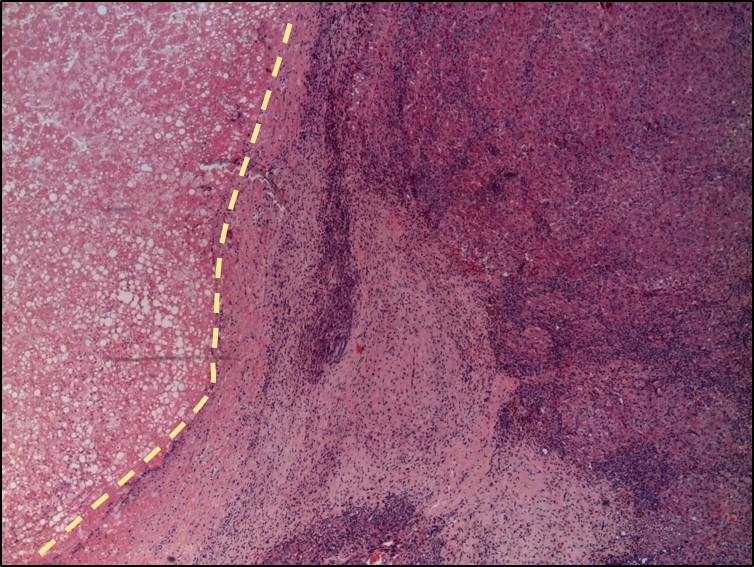

Histological staining of a liver cancer in a mouse.